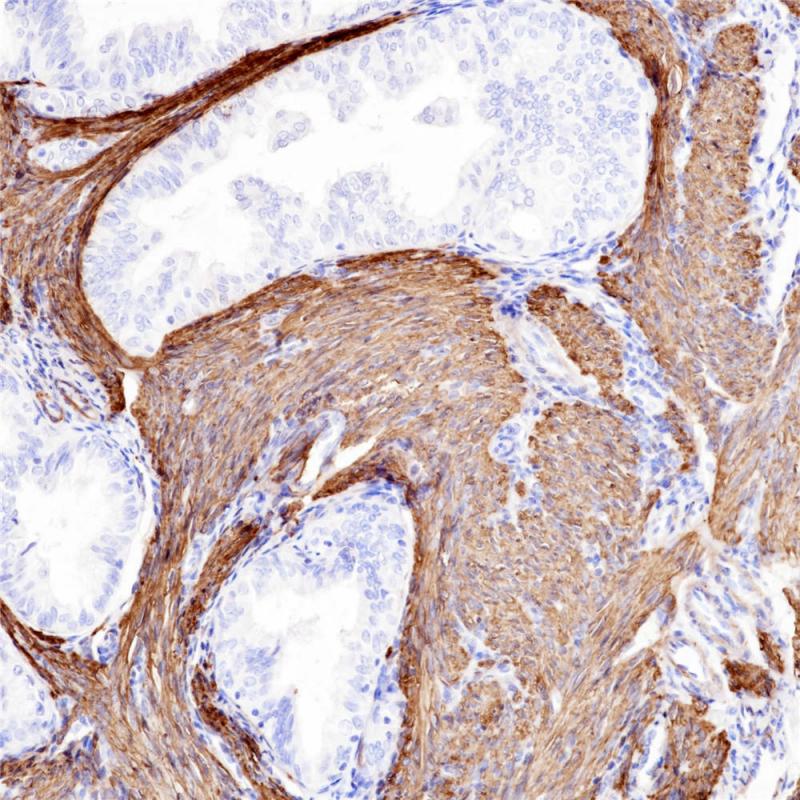

Calponin是一种结合原肌球蛋白和F-肌动蛋白的钙调蛋白,是平滑肌细胞的一种特异性蛋白,具有调节平滑肌收缩的功能。Calponin在正常的平滑肌细胞及肌上皮细胞中呈阳性表达,结缔组织增生的间质中肌纤维母细胞会阳性表达。该抗体主要用于平滑肌瘤和乳腺病变中肌上皮细胞的诊断和研究。

阳性对照

子宫肌瘤